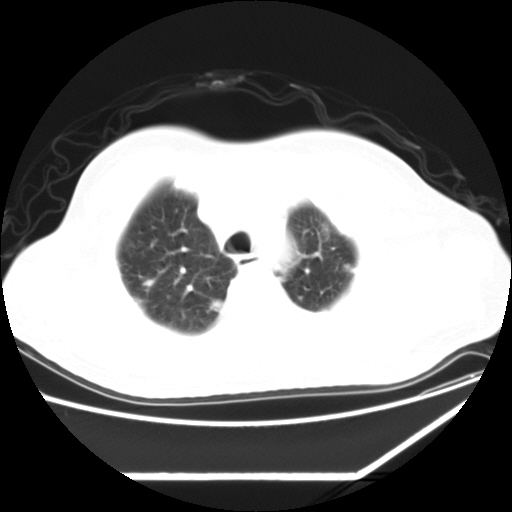

男,57,畏寒,发热

两侧多发肺脓肿,两侧胸膜增厚,抗炎治疗后复查

双肺多发结节样病灶,部分内见透光区,纵隔内见淋巴结肿大。结核临床如有畏寒,高热,白细胞增高首先考虑迁徙性肺脓肿(多是金黄色葡萄球菌感染)。

注意除外转移瘤。

1)考虑两肺感染性病变(金黄色葡萄球菌肺炎?);建议抗炎治疗后复查排除其他。2)双侧少量胸腔积液。

双肺典型的亚急性粟粒性肺结核

双侧胸膜结核